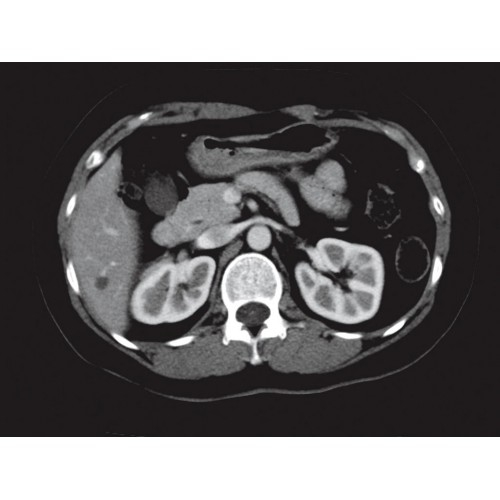

Современный 32-срезовый компьютерный томограф для точной диагностики. Обеспечивает высокое качество изображения при сниженной лучевой нагрузке. Удобный и надежный в эксплуатации. Подходит для широкого спектра диагностических исследований.

Компьютерный томограф GE Brivo CT385 представляет собой современное диагностическое оборудование, сочетающее высокую точность исследований с повышенным комфортом для пациентов. Этот аппарат открывает новые возможности для детальной визуализации анатомических структур.

Области применения

Позволяет проводить комплексные исследования всех анатомических зон, включая нейровизуализацию, ангиографию, исследования органов грудной и брюшной полости. Особенно эффективен для раннего выявления онкологических заболеваний.